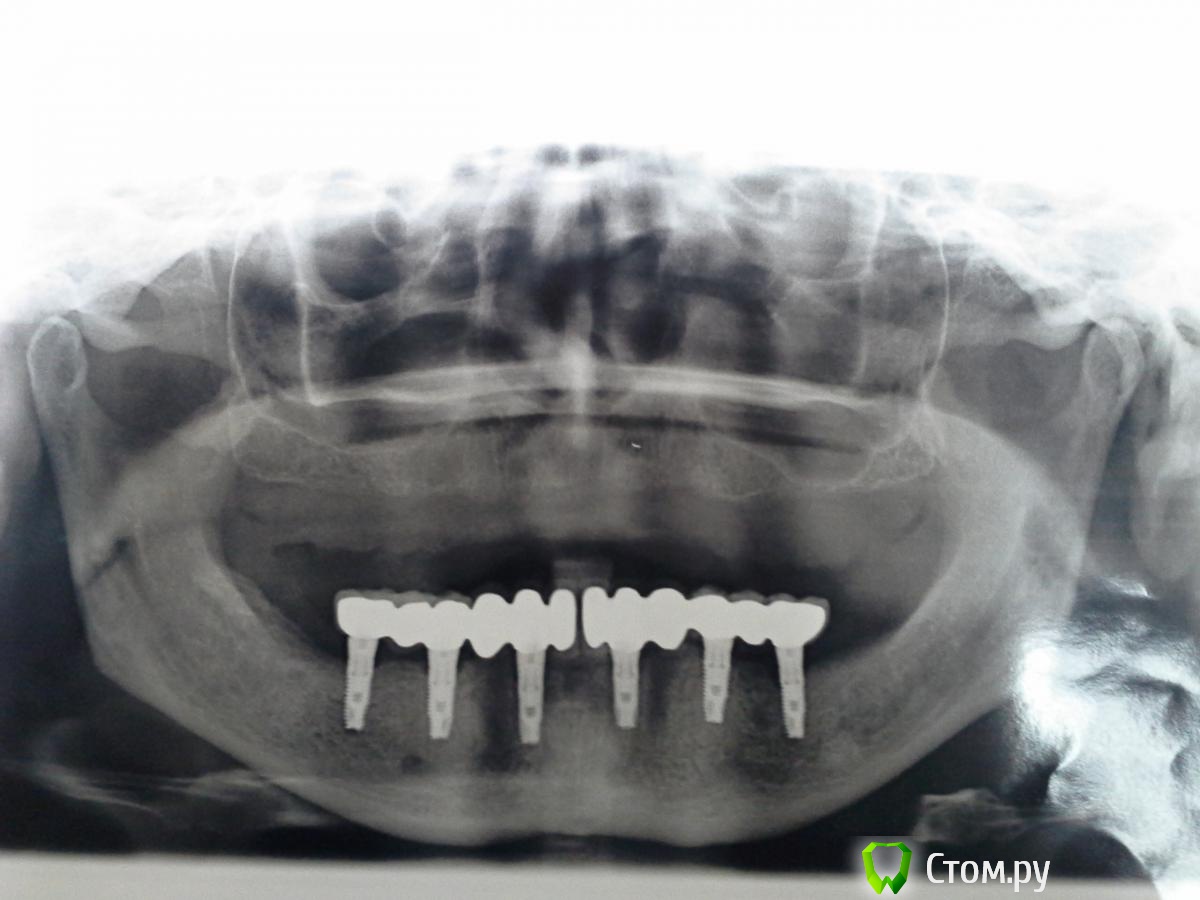

Magomed Опубликовано 3 сентября, 2014 Поделиться Опубликовано 3 сентября, 2014 (изменено) работу делал год. в.ч.удалил 8 з. низ 6 з. в.ч. каркас фрезеров. низ литьё. Изменено 3 сентября, 2014 пользователем Magomed Ссылка на комментарий

Magomed Опубликовано 5 сентября, 2014 Автор Поделиться Опубликовано 5 сентября, 2014 Здравствуйте, сколько прошло от момента имплантации верх и них и от протезирования верх и низ?низ 8 мес. верх 2 нед. протезирования Ссылка на комментарий